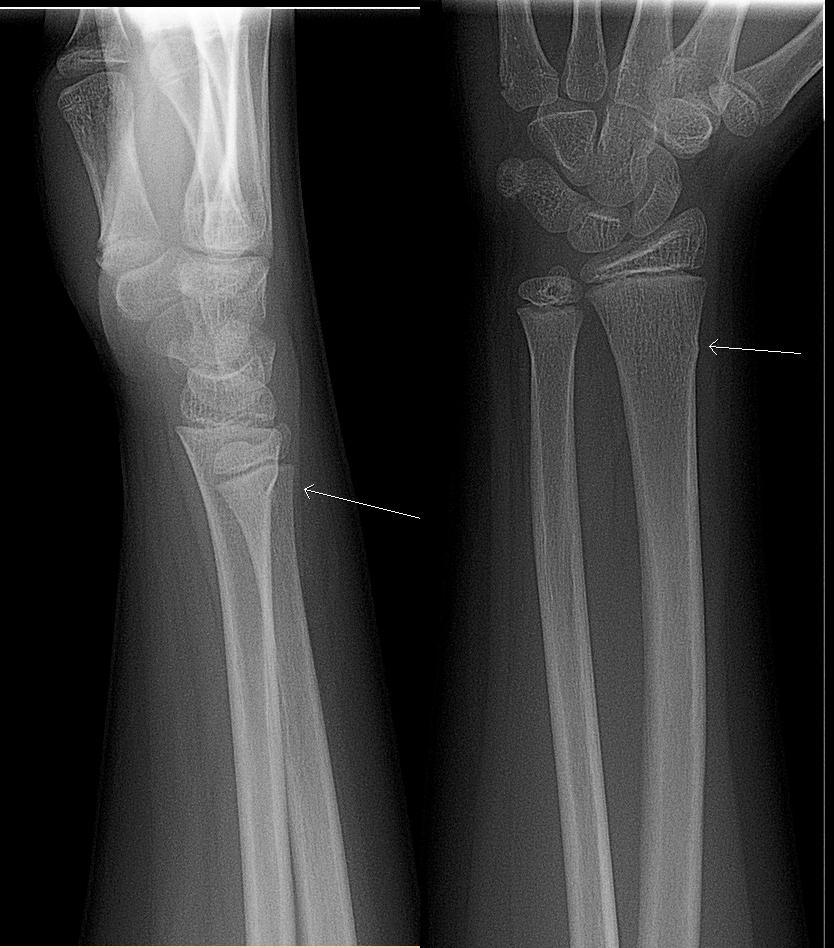

Il arrive souvent que l'os de l'avant-bras d'un enfant ne se brise pas complètement, mais se déforme simplement à la surface. C'est ce qu'on appelle une fracture "en bâton vert", qui ne nécessite pas d'opération : elle guérit dans un plâtre. Cette radiographie montre une fracture en bâton vert au niveau de la flèche blanche : il s'agit d'un petit renflement du bord de l'os, plutôt que d'une fracture complète :

Fracture du bâton vert

© Lucien Monfils, CC BY-SA 3.0, via Wikimedia Commons

Par Lucien Monfils (Travail personnel), CC BY-SA 3.0via Wikimedia Commons